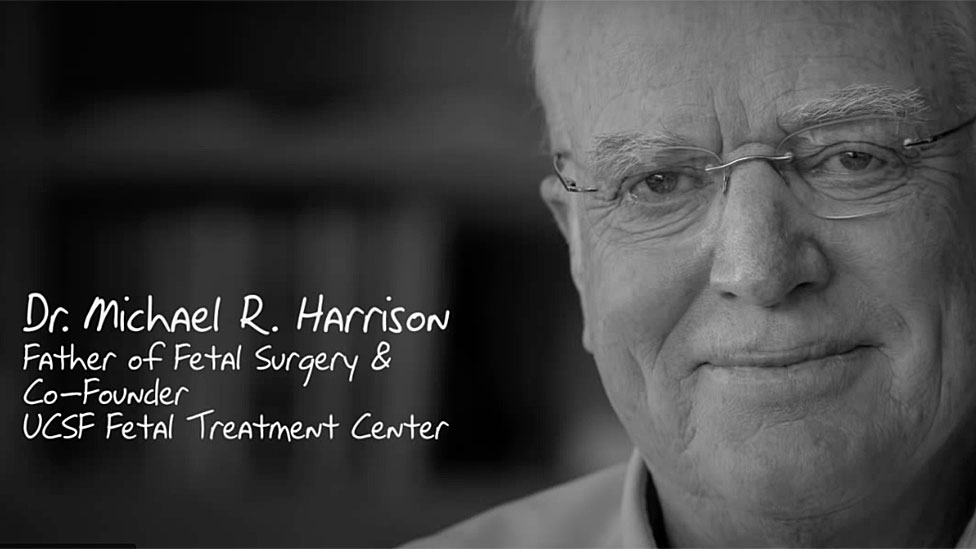

El médico que lo operó, Michael Harrison, desarrolló la técnica de la cirugía intrauterina trabajando en el Hospital de Niños de la Universidad de California en San Francisco (UCSF).

Harrison le contó recientemente al programa de radio Witness, del Servicio Mundial de la BBC, por qué le pareció necesario buscar la manera de operar al feto cuando todavía estaba en la panza, a pesar de todos los riesgos.

"Hoy podemos hacer el procedimiento en media hora o una hora", contó el experto, quien —por razones obvias— es reconocido en todo el mundo como el "Padre de la Cirugía Fetal".